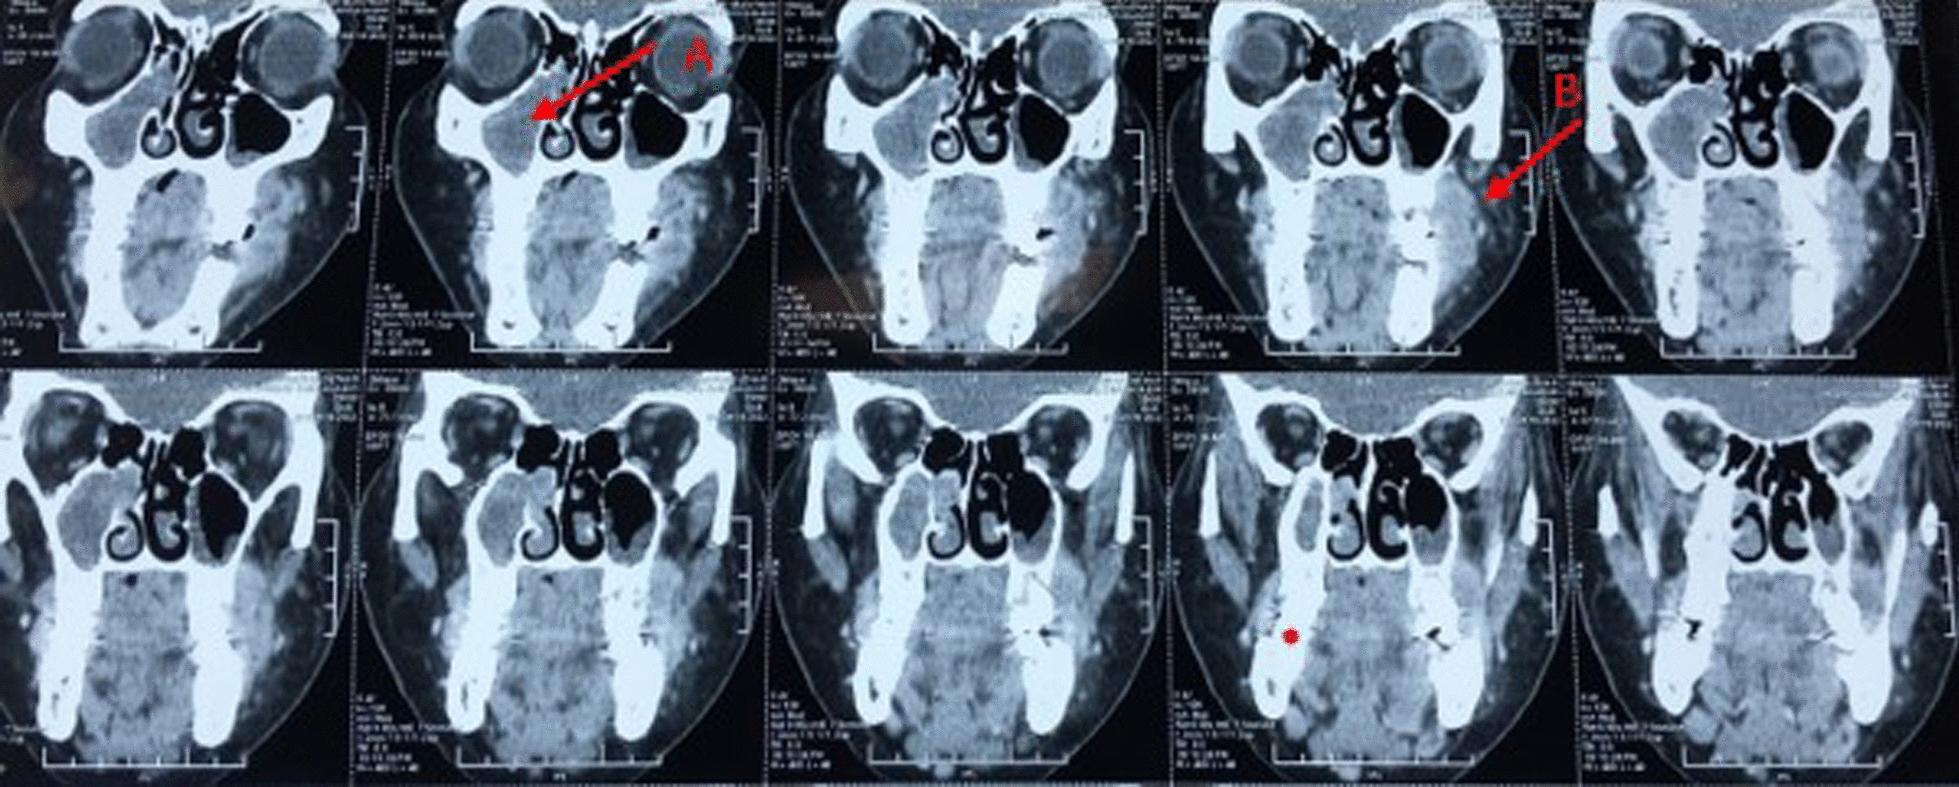

We report the case of a 26-years-old Caucasian Moroccan woman with oral Burkitt lymphoma without any other general symptoms. It presented as swelling of the left mandibular and maxillary soft tissue progressing for 1 month. The unilateral location in both maxilla and mandible is an atypical feature. The diagnosis was based on clinical and radiographic features. Furthermore, the histopathological examination and immunochemistry was of paramount importance for making the final diagnosis of oral Burkitt lymphoma.

我们报告一例26岁的摩洛哥裔白种女性患有口腔伯基特淋巴瘤,无任何其他全身症状。表现为左下颌和上颌软组织肿胀,病程1个月。上颌和下颌均为单侧发病是其非典型特征。诊断基于临床和影像学特征。此外,组织病理学检查和免疫化学对于口腔伯基特淋巴瘤的最终诊断至关重要。